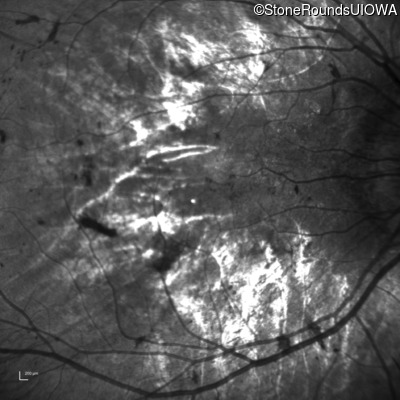

This 12 year old girl has had poor night vision and subnormal acuity since she was about 3 years old.

| Age at visit: 12 years (Visit 2) |